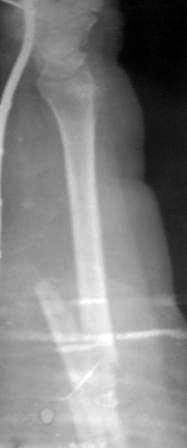

Пациентка 49 лет, по поводу перелома обеих костей предплечья оперирована в марте месяце « и/м остеосинтез спицами», через 4 месяца спицы удалены , антибиотикотерапия и фиксация гипсовой повязкой продолжена, но, учитывая что образуются ложный сустав, госпитализирована.

Повторно открывать зону перелома никак не хочется, учитывая р-картину! А что если закрыто рассверливать к/м канал ( как при БИОС), и КДО аппаратом Илизарова?

Уважаемые коллеги помогите советом! Извиняюсь за плохое качество р-снимков!